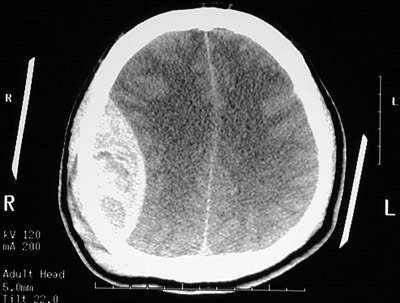

| In this axial head CT scan without contrast there is a large epidural hematoma on the right, with a "lens shaped" outline as the smooth dura is indented against the underlying cortex. The acute blood collection appears bright on CT. This patient fell from a height and struck the right side of his head, severing the middle meningeal artery. This epidural hematoma collected within hours. In the view seen below, at a level higher than the view above, there is a midline shift of the falx cerebri. |